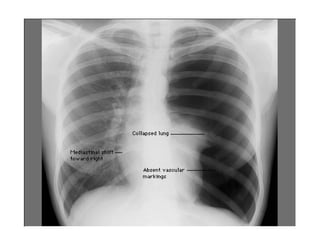

Finally, Check the Lung Fields

• Infiltrates

• Increased interstitial markings

• Masses

• Absence of normal margins

• Air bronchograms

• Increased vascularity

Chest x ray